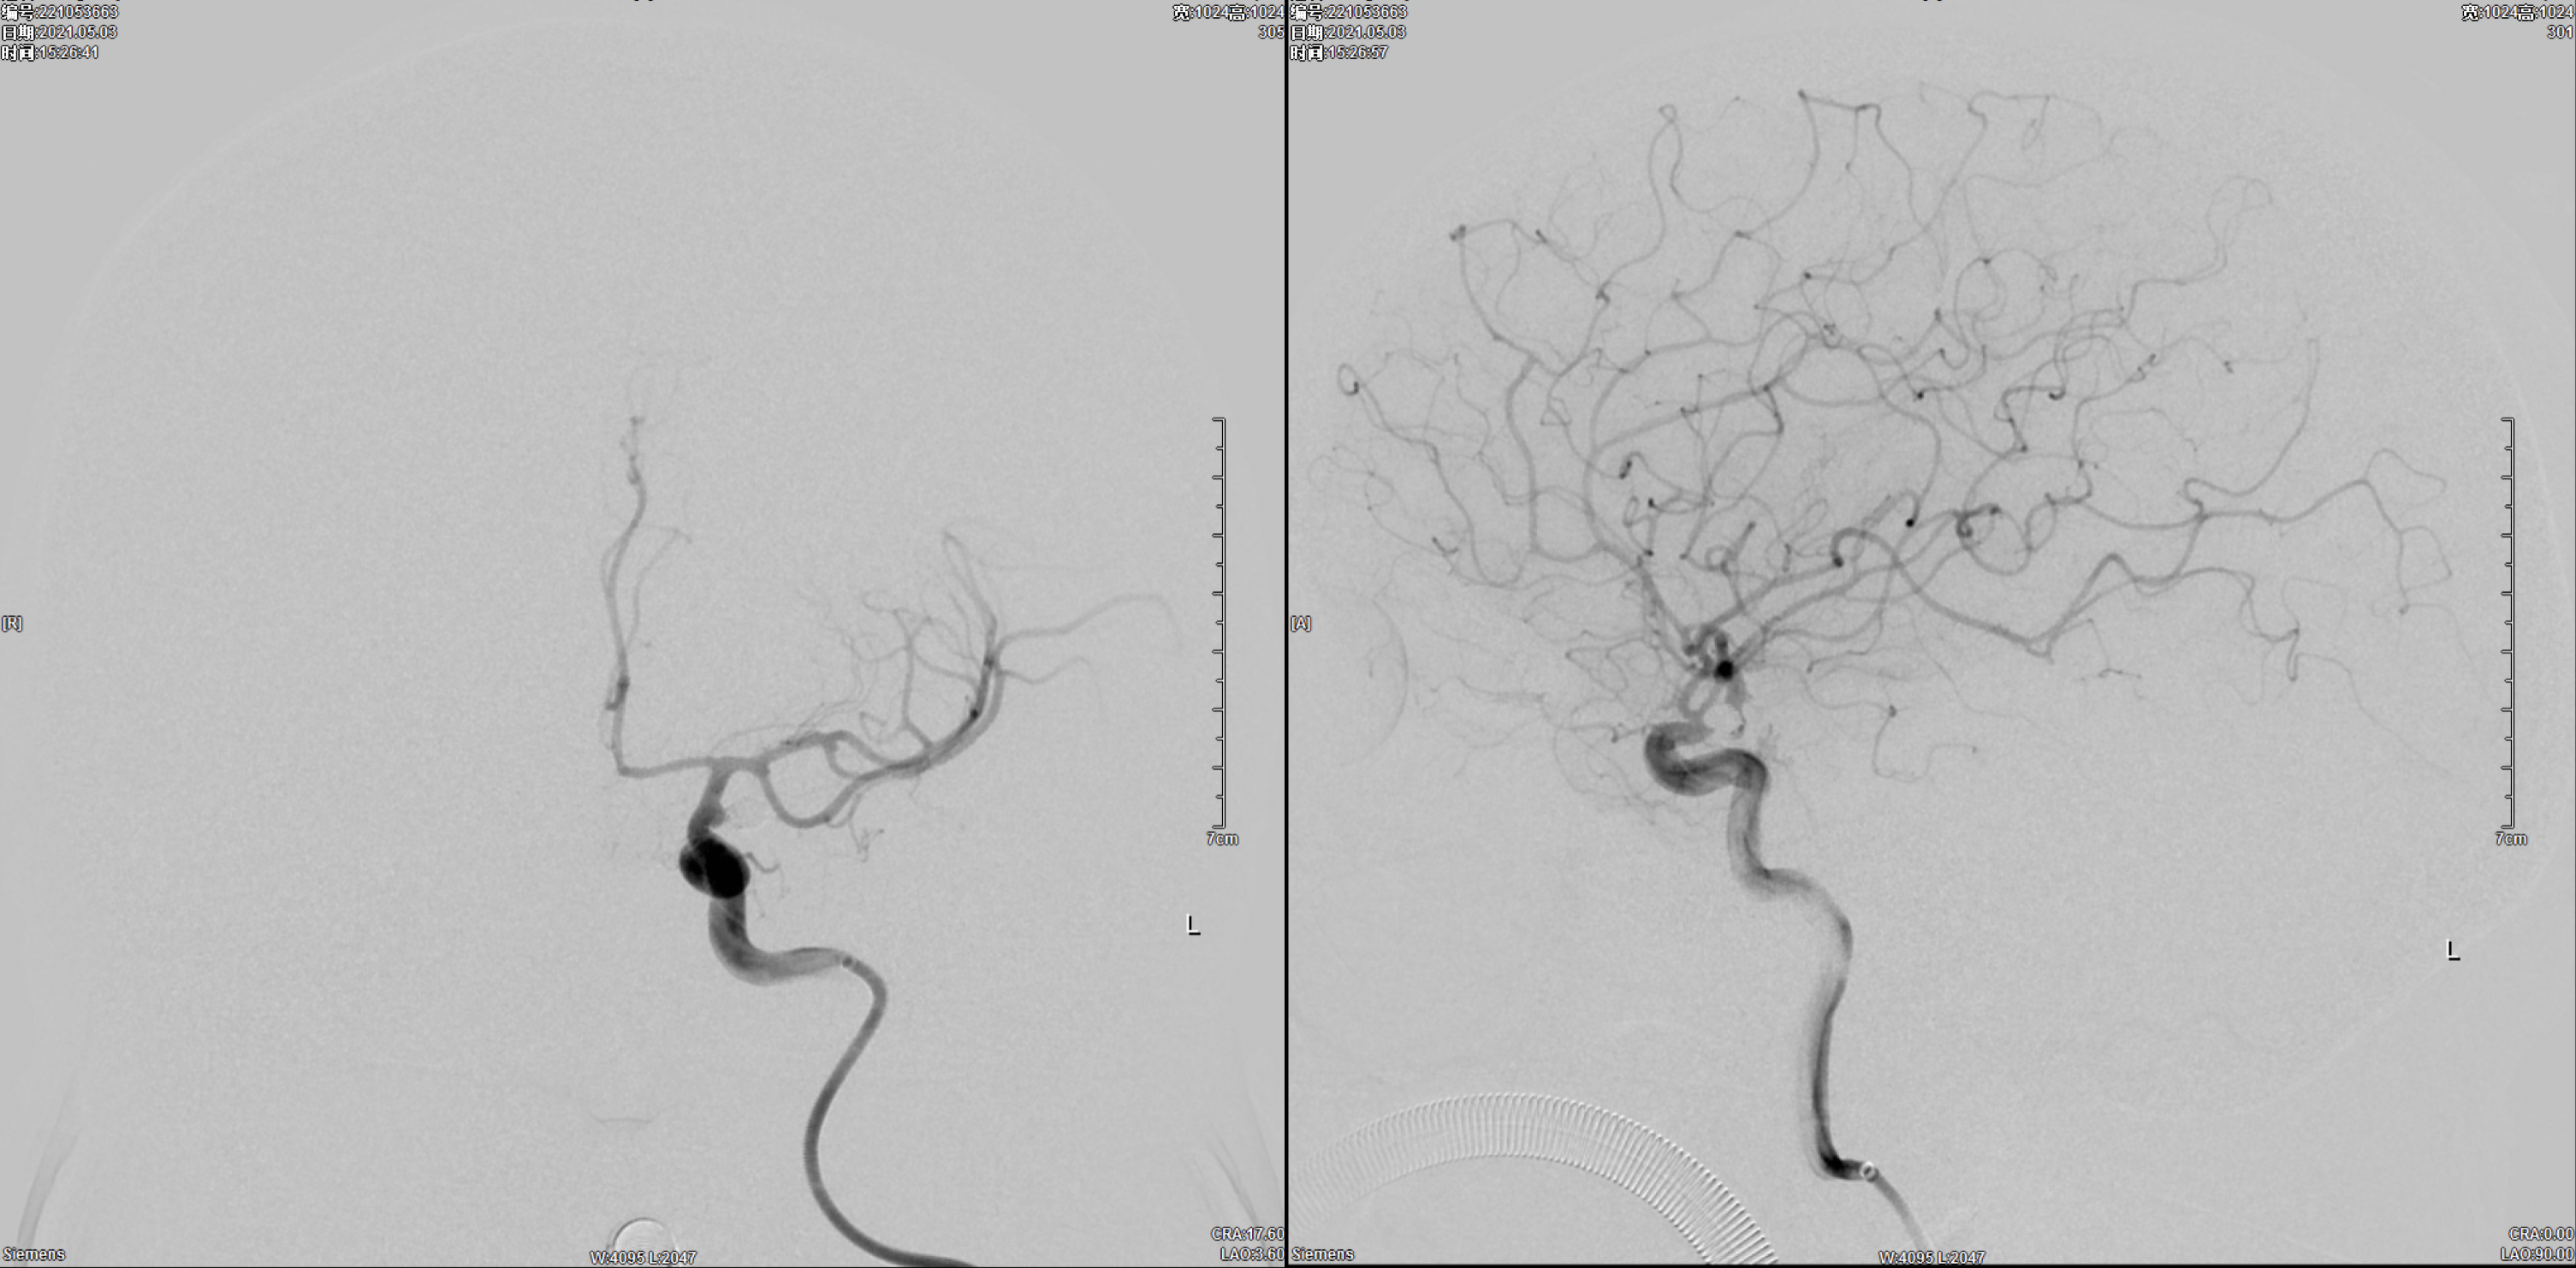

右侧颈内动脉正侧位造影:颈内动脉多发动脉瘤(眼动脉段及后交通段)。

左侧颈内动脉正侧位造影:颈内动脉后交通动脉瘤。